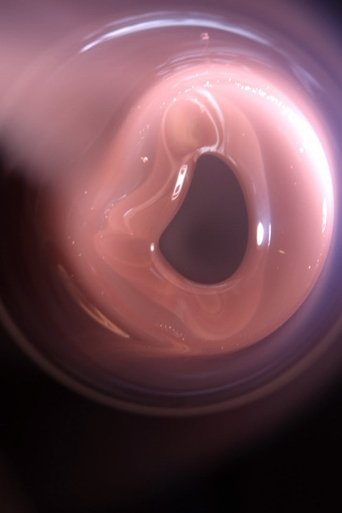

An image from The Body Blow, one of the productions that also features Ilona Sagar.

The Body Blow

2024